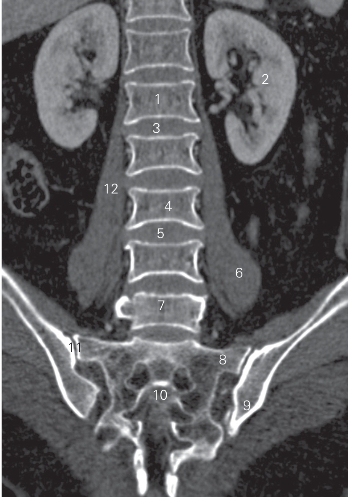

图3-7 经腰椎椎体的冠状曲面重建CT图像(骨窗)

1 第1腰椎椎体 1st vertebral body 2 左肾 left kidney

3 第1腰椎间盘 1st lumbar intervertebral disc

4 第3腰椎椎体 3rd lumbar vertebral body

5 第3腰椎间盘 3rd lumbar intervertebral disc

6 左侧腰大肌 left psoas major

7 第5腰椎椎体 5th lumbar vertebral body

8 骶翼 ala of sacrum

9 髂骨 ilium 10 第2骶骨 2nd sacrum

11 骶髂关节 sacroiliac joint 12 右侧腰大肌 right psoas major